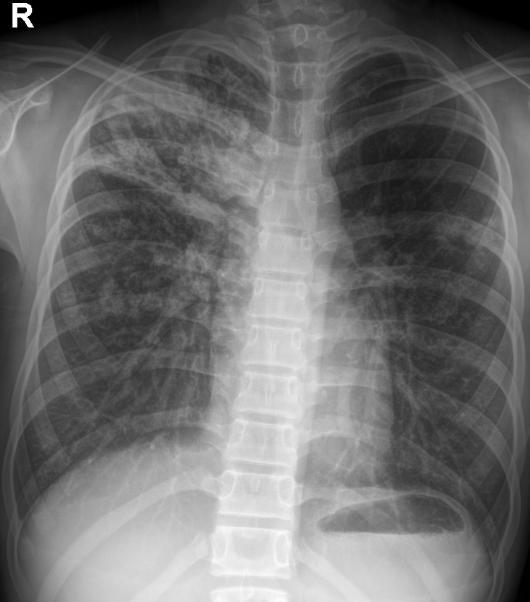

我的好友丹丹,老家有一个表妹,今年16岁,1年前无明显诱因出现右臀部酸痛,伴畏寒、发热、午后低热、盗汗,无双下肢放射痛,并出现左臀部皮肤红肿、破溃、流脓,曾在当地卫生院间断诊治,予以口服药物治疗,效果差,后逐渐出现右臀部外侧皮肤破溃、流脓,经自行口服药物后窦道自行愈合后,周围再次出现流脓,经久不愈,时有脓液流出。丹丹前两天回到老家,把表妹接到我院住院治疗。骨科专科检查发现右臀部一个约0.5x0 5 cm大小窦道口,按压周围可见黄色干酪样分泌物流出,局部可见肉芽组织,无红肿,周围可见多个窦道口疤痕。胸部X线检查:右上.中肺野及左中肺野可见片状.斑片(点)状.条索状阴影,边缘清晰,密度均匀。骨盆CT检查:右侧骶髂关节面骨质破坏、硬化,正常关节结构破坏,臀部软组织内可见囊性密度不均之肿块,影像诊断:右上.中肺.左中肺结核,右侧骶髂关节结核伴髂内肌冷脓肿形成、关节半脱位。

骶髂关节结核常见影像学表现为骨质破坏,死骨形成,关节间隙增宽或变窄,周围脓肿形成,部分伴有窦道。骨盆的X线平片检查可明显的看出骨质的改变,部分脓肿,但由于解剖结构的特殊性,无法显示全部的关节间隙。CT的密度分辨率较高,能够清晰的显示骨破坏程度、部位以及范围,对死骨、脓肿的形成及部位、窦道、囊肿等能够直观的检查,可以发现到X线检查难以观测的生理性骨化和病理性改变。